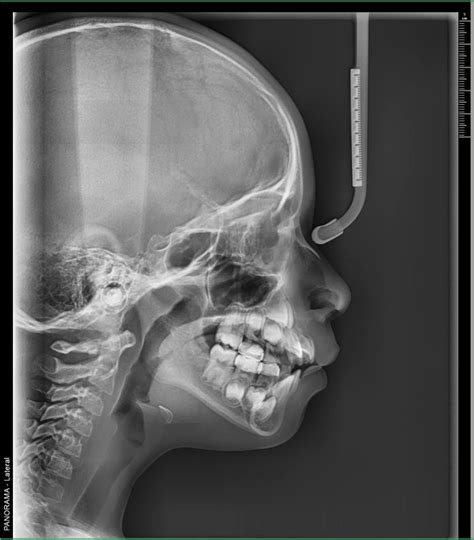

Las radiografías extraorales son técnicas de diagnóstico por imagen en odontología en las que el sensor o película radiográfica se coloca fuera de la boca del paciente. Es fundamental para los análisis cefalométricos que determinan la posición y alineación de los dientes, así como la relación entre los maxilares y el cráneo.

- Radiografía lateral del cráneo o telerradiografía: Es una radiografía lateral que abarca la totalidad del cráneo. Se emplea sobre todo para valorar aspectos como el desarrollo de las mandíbulas, los problemas de posición y la relación intermaxilar. Son un tipo de radiografía panorámica muy empleado en los tratamientos con ortodoncias.